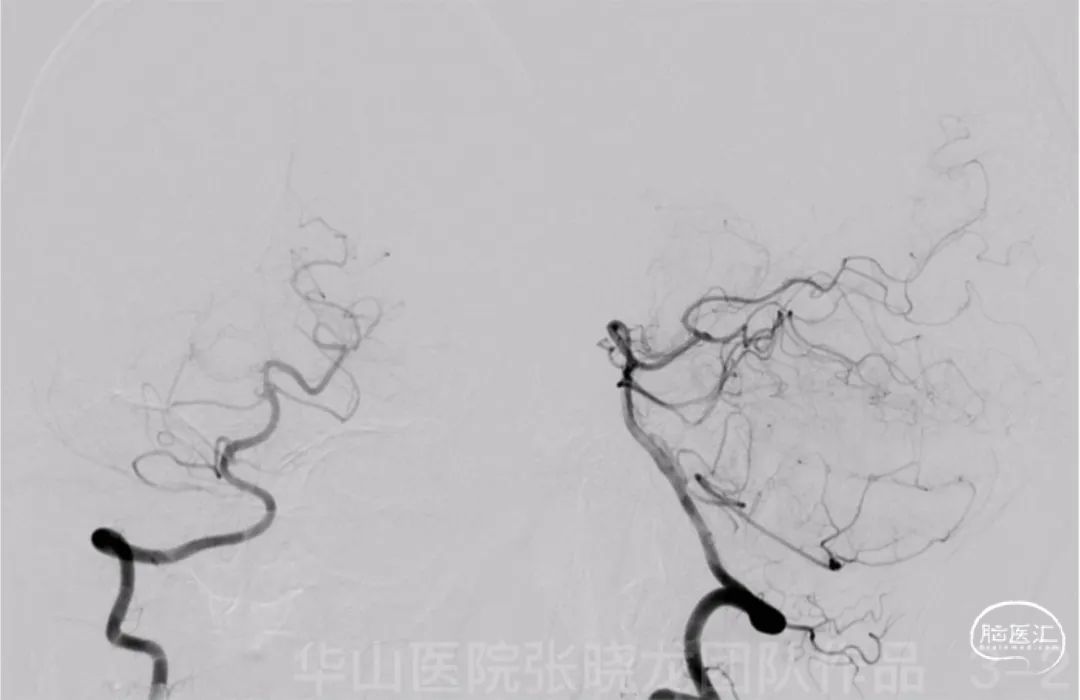

Figure 3 GIF. DSA confirmed a right fetal-type posterior communicating artery aneurysm with a relative wide neck. Right P1 segment was undeveloped.

图 3 GIF. DSA证实右侧胚胎型后交通宽颈动脉瘤。右侧P1段未发育。